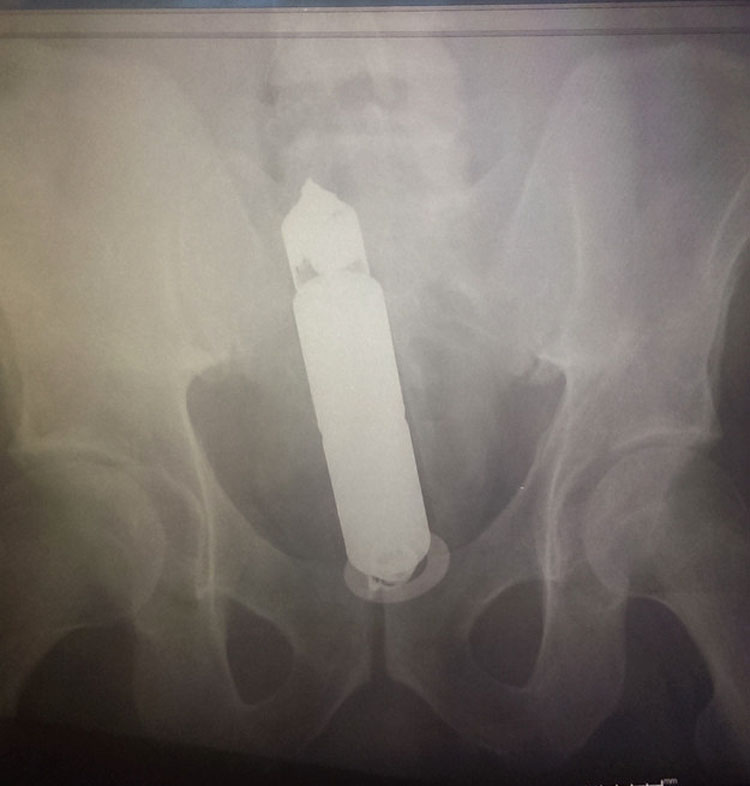

No vamos a cuestionar las motivaciones que una persona puede tener para introducirse por «cierta» parte del cuerpo algunos de los siguientes objetos que vamos a ver.

Pero de lo que sí podemos dar fe es de la veracidad de estas imágenes obtenidas clínicamente mediante el uso de Rayos-X.

Verlo para creerlo… 22 objetos que algunas personas se introdujeron en el… cuerpo.

15. Una bombilla.